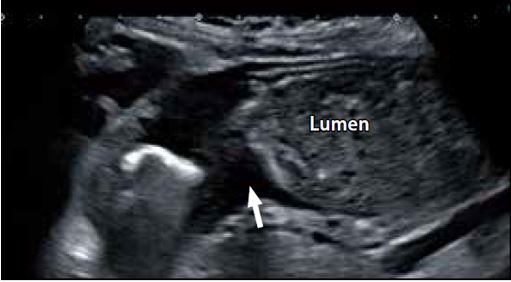

Запущений рак шлунку та запущений рак прямої кишки

Ультраширокосмуговий датчик показує менше артефактів і має вищий коефіцієнт співвідношення сигнал/шум (SNR). Ці особливості роблять його ідеальним для ультразвукового дослідження шлунково-кишкового тракту, який майже завжди схильний до появи артефактів, спричинених багаторазовим відбиттям від стінок тіла та бічних ділянок від інтралюмінального газу. У випадку запущеного раку шлунку (рис. 8а) чітко видно осередкове потовщення стінки та порушення структури пристінного шару. Аналогічно, при запущеному раку прямої кишки (рис. 8б) чітко видно осередкове потовщення стінки і порушення структури пристінкового шару.

a) Запущений рак шлунку

б) Запущений рак прямої кишки

Рисунок 8. Запущений рак шлунку (а) і запущений рак прямої кишки (б)